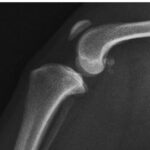

身体検査にて腫れや疼痛が見られる骨や関節部位のレントゲン検査を実施します。

典型的なレントゲン所見としては骨の融解と骨髄の拡大、骨を覆っている骨膜が毛羽だった不整構造を示すようになるなどといった通称サンバーストと呼ばれる所見が見られます。

また、症例によっては腫瘍による病的骨折も確認されることがあります。

発生部位やレントゲン所見から骨肉腫、骨肉腫以外の原発性腫瘍、真菌や細菌感染による炎症病変などを見分けていきます。